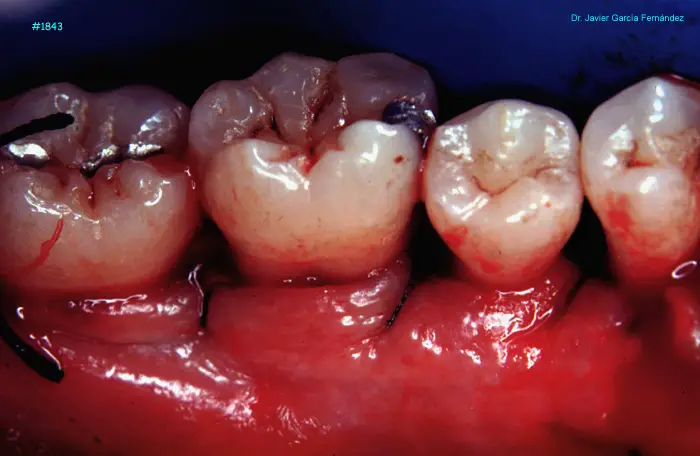

image 109